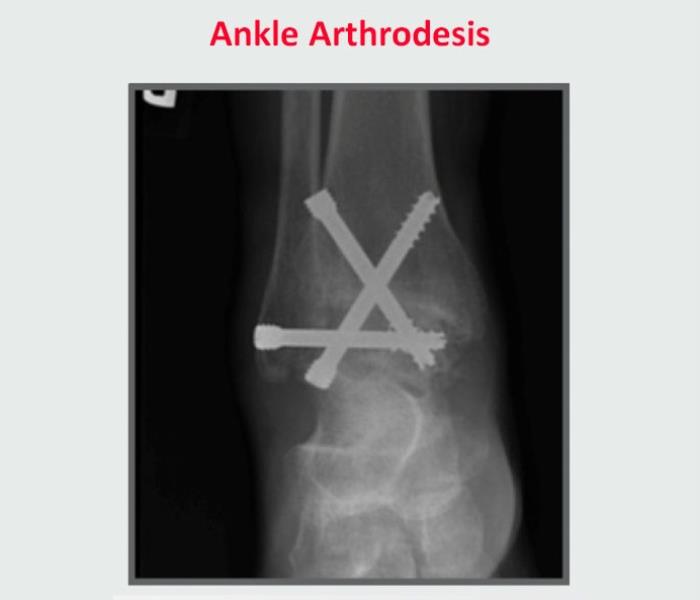

Ankle fusion (arthrodesis) involves cleaning the worn-out ankle joint and fusing the bones together with screws, plates, and bone grafts. Ankle fusion relieves pain, but it also limits your ankle’s range of motion, Parekh explained. The limited mobility can change how you walk, and that can cause wear and tear, and ultimately painful arthritis, in other parts of your ankle, knee, and foot. Recovery is longer with ankle fusion than ankle replacement. Patients can spend up to 10 to 12 weeks in a cast. Because the ankle joint is locked in place, physical therapy is not part of the recovery process.

Ankle replacement is a newer option. The procedure, also known as ankle arthroplasty, replaces the arthritic ankle joint with a metal and plastic prosthesis. The recovery period is shorter than ankle fusion – typically three to six weeks in a cast followed by physical therapy. People regain a much wider range of motion; most return to active lifestyles. While the artificial ankle can wear out and may need to be replaced, research shows 90 percent are still functioning well 10 years after surgery.